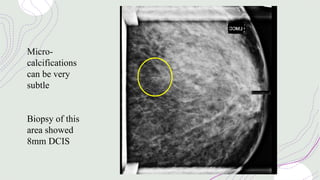

Micro-

calcifications

can be very

subtle

Biopsy of this

area showed

8mm DCIS

Mammograms may oftenshow areas of calcification, these may be malignant. In ductal carcinoma in situ (DCIS), there is normally no mass but just an area of calcification